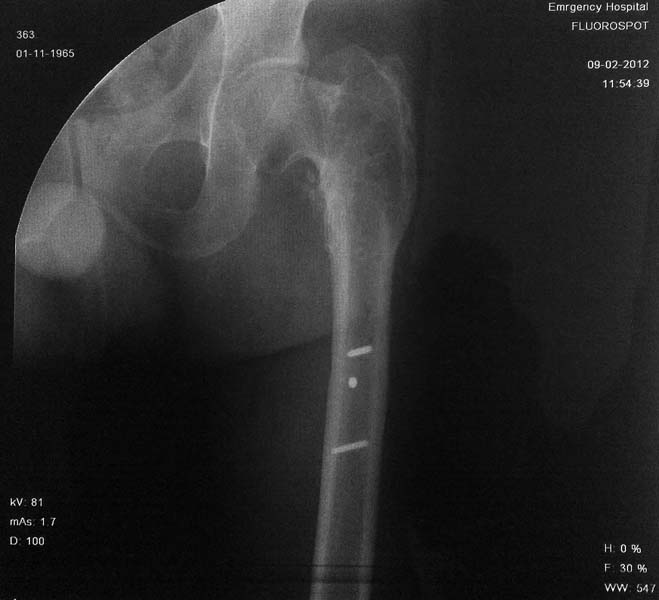

Рентгенограмма пациента А 49 лет с диагнозом: Неправильно консолидированный подвертельный перелом левой бедренной кости, с варусной деформацией.

На рентгенограммах левого тазобедренного сустава шеечно-диафизарный угол 90 градус. Признаки артроза 2 ст и очаг остеосклероза в проекции ШДУ (указан стрелкой).